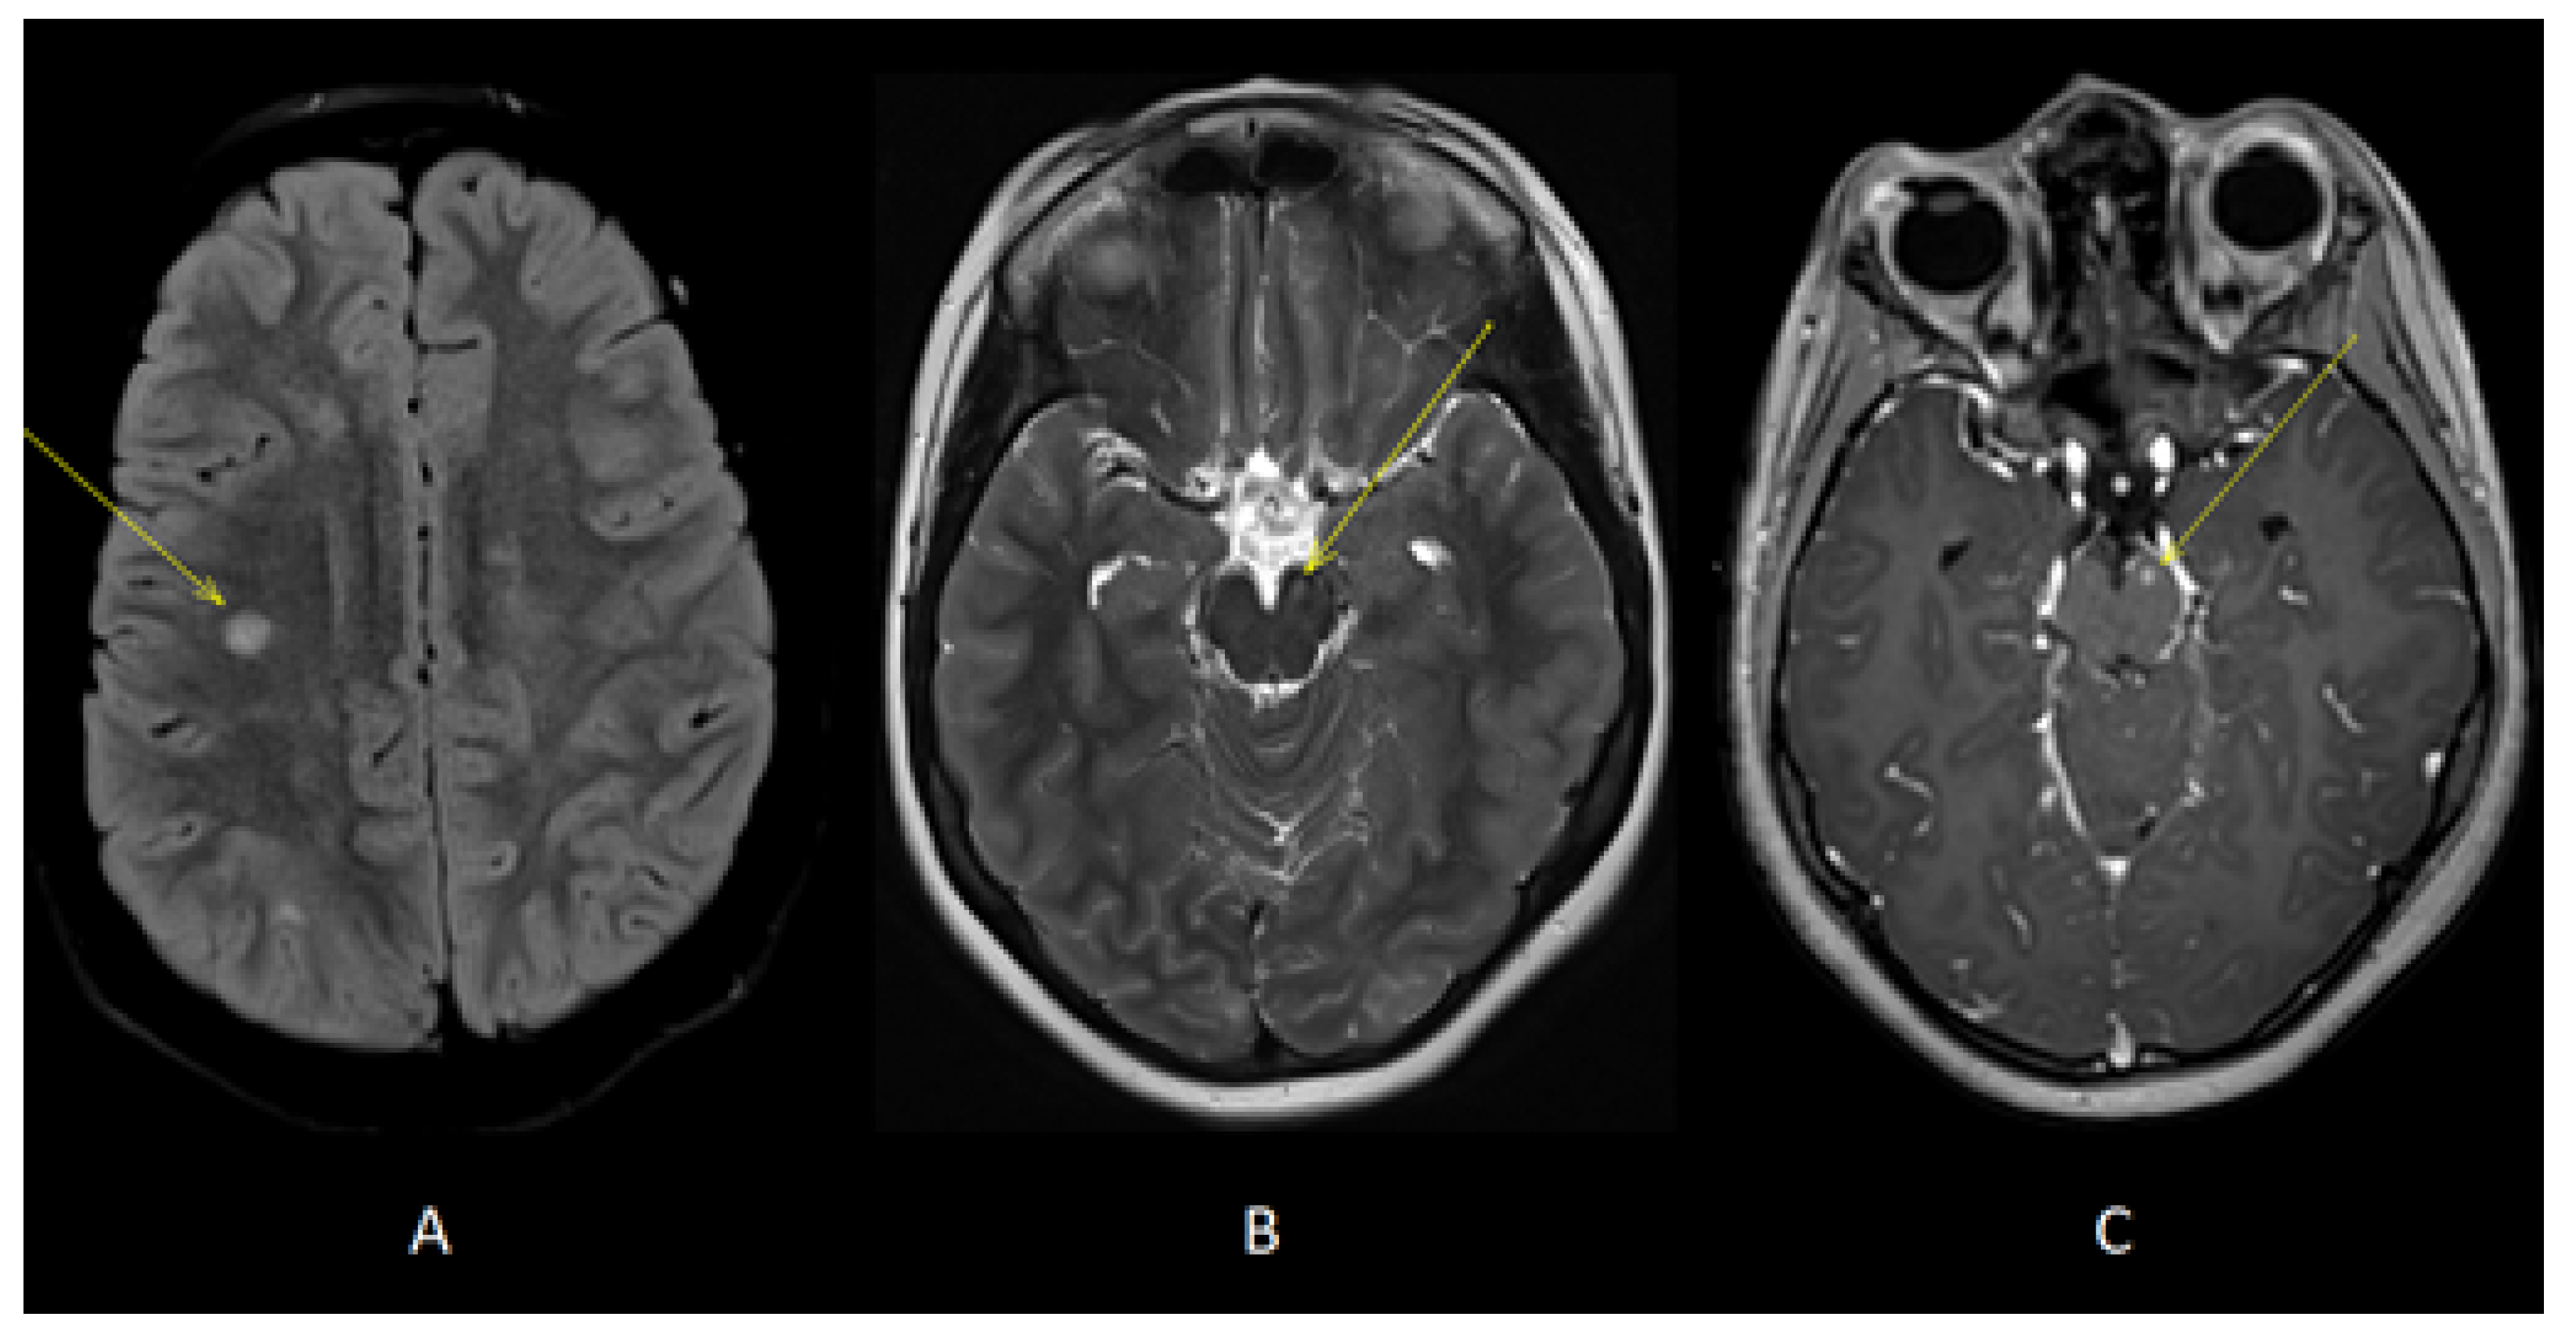

Figure 3.

Axial T2-FLAIR (A) and T2 (B) images showed additional lesions in right deep frontal white matter (yellow arrow, A) and left cerebral peduncle (yellow arrow, B). Axial T1 images acquired after gadolinium administration (C) showed enhancement of the lesion located in left cerebral peduncle (yellow arrow).